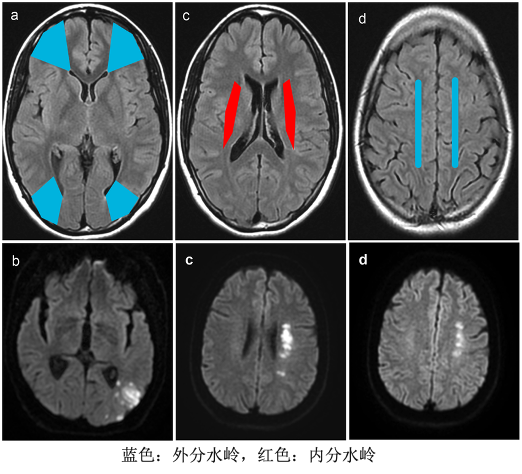

3. 分水岭脑梗死:

脑动脉(ACA、MCA、PCA)交界处毛细血管吻合网往往成带状分布,称之为分水岭/边缘带或者低压带。

分水岭脑梗死:相邻2条或者3条脑动脉供血区或者基底节区深穿动脉供血的边缘带局限性缺血造成的脑梗死

分型:内分水岭梗死(皮质下型)和外分水岭梗死(皮质型)

病因:颅内外动脉严重狭窄或闭塞(>70%)、低血压低灌注等原因导致的血液动力学障碍(皮质下型),皮质型的发生更多与微栓子清除障碍有关。

分布在血管的分水岭区,多累及单侧,少见累及双侧,颈部及颅内血管检查有血管严重狭窄的证据,临床可有低血压及低血容量的证据。